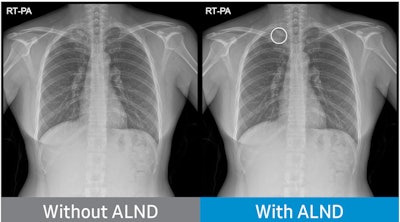

Chest radiograph without Auto Lung Nodule Detection (ALND) and chest radiograph with lung nodule marked. Image courtesy of Neuologica.In international clinical trials, ALND achieved a sensitivity of at least 80% identifying lung cancer in 600 chest x-rays, the company said.